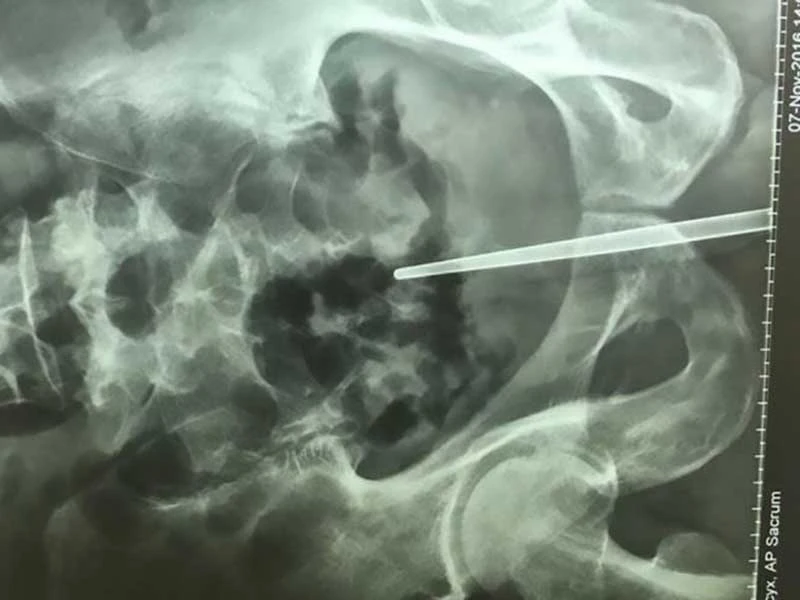

Hình ảnh chụp cắt lớp cho thấy cây đũa đã bị nhét tới tận thành trực tràng ông này. Theo các bác sĩ, nếu cây đũa bị đẩy sâu thêm chút nữa thì rất có thể ông Chen đã tử vong.

Các bác sĩ phải phẫu thuật mới lôi được cây đũa dài 18 cm làm bằng kim loại không thấm nước ra khỏi dương vật ông Chen chơi dại này. Hiện ông Chen đang hồi phục dần trong bệnh viện, tuy nhiên các bác sĩ chưa thể khẳng định ông có bị di chứng gì sau này không.